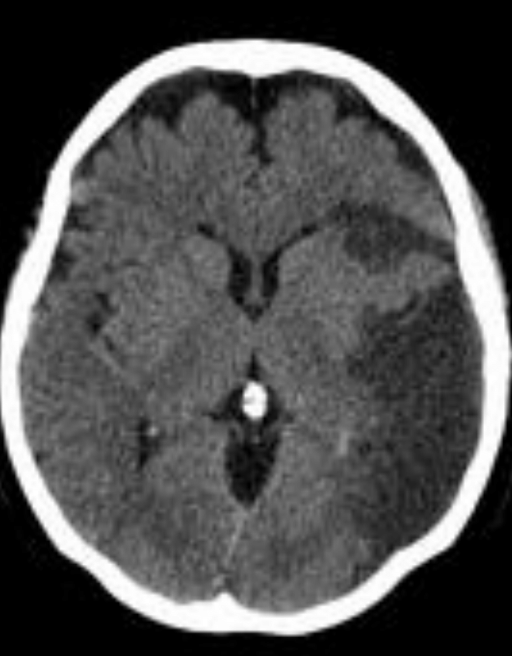

¿Qué fase es? ¿Qué signo ves?

Fase aguda, efecto de masa